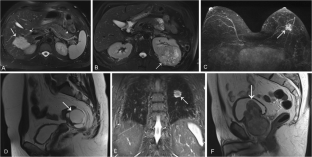

Fig. 4